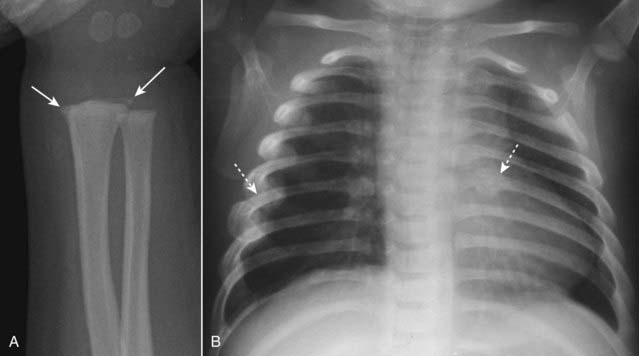

Metaphyseal corner fractures. Small, avulsion-type fractures of the metaphyses due to rapid rotation of ligamentous insertions, corner fractures are considered diagnostic of physical abuse. They can parallel the metaphysis and have a bucket-handle appearance (Fig. 22-19A).

Rib fractures, especially multiple fractures and fractures of the posterior ribs (which rarely fracture even due to accidental trauma) (Fig. 22-19B).

Figure 22-19 Child abuse.

A, There are metaphyseal corner fractures (solid white arrows), small avulsion-type fractures of the distal radius, a finding characteristic of child abuse. B, There are several healing rib fractures (dotted white arrows), including one involving the left 6th posterior rib. Fractures of the posterior ribs are unusual, even in accidental trauma, and should raise suspicion for child abuse.